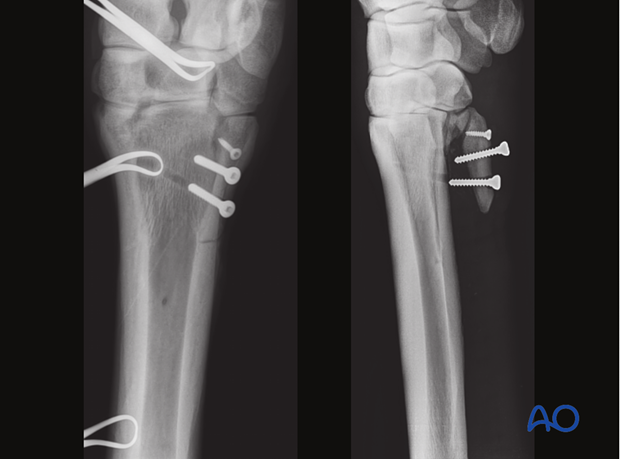

Screws may engage only the splint bone (left) or include the near cortex of the third metacarpal/metatarsal bone (right).

The fusion of the splint bone with the third metacarpal/metatarsal bone results in joint stability; however, this is not ideal from a physiological standpoint because it eliminates normal micro-movement within the joint and between the splint bone and the third metacarpal/metatarsal bone.

Therefore, whenever possible the screws should only engage the fractured bone.

Screws can only be used in simple oblique and minimally displaced splint bone fractures, because screw fixation alone is generally associated with a relatively high rate of technical failure. The application of a plate is the preferred treatment, however, because it serves as a tension band when fixed also to the distal fragment.

In Warmblood-, Thoroughbred-, Arabian- and American Quarter horses 3.5 mm screws should be used. In small Islandic horses, ponies or foals 2.7 mm screws can be used.

Usually, two screws can be used. If possible, a third screw should be introduced to improve the stability of the fixation.

Example of a postoperative complication with fixation failure.

In this case, screws were also inserted into the third metacarpal/-tarsal bone. Screws without a plate are too fractious to achieve stable fixation of the splint bone to the third metacarpal/-tarsal bone.